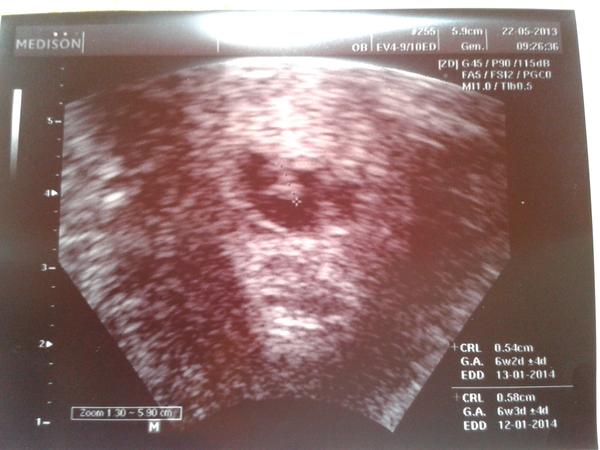

Ahoj holky tak jsem zpět...bylo to náročné....hcg nestoupla podle představ doktora ,ale udělal utz pro vyloučení mimoděložního....jaké překvapení na nás vykouklo....zavolal i přítele ať se jde podívat na zázrak...holky a ono mělo i náznak srdíčka!!!!minule ani bublinka a teď toto. Tak teď už je to na bojovníčkovi jak to zvládne....

Moc vám všem děkuji za podporu. nemám sice jistotu ,že to bude ok. ,ale je naděje.